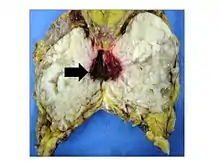

Phyllodes tumor

Phyllodes tumors (from Greek: phullon leaf), also cystosarcoma phyllodes, cystosarcoma phylloides and phylloides tumor, are typically large, fast-growing masses that form from the periductal stromal cells of the breast. They account for less than 1% of all breast neoplasms.

Phyllodes tumors are a fibroepithelial tumor composed of an epithelial and a cellular stromal component. They may be considered benign, borderline, or malignant depending on histologic features including stromal cellularity, infiltration at the tumor's edge, and mitotic activity.[1] All forms of phyllodes tumors are regarded as having malignant potential. A large series from the M.D. Anderson Cancer Centre reported the incidence of each as benign (58%), borderline (12%), and malignant (30%). Malignant phyllodes tumours behave like sarcomas and can develop blood-borne metastases. Approximately 10% of patients with phyllodes tumours develop distant metastases and this can go up to 20% in patients with histologically malignant tumours.[2] The commonest sites for distant metastases are the lung, bone, and abdominal viscera. Rare sites of metastasis, such as to the parotid region, have also been described.[3]